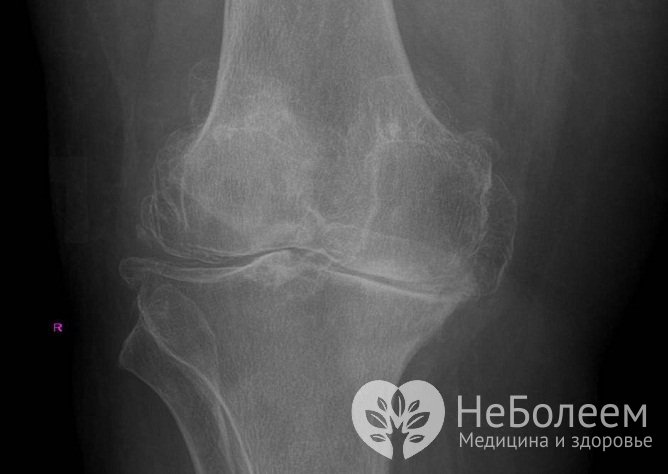

Для уточнения диагноза, а также с целью определения степени артроза коленного сустава и дифференциальной диагностики заболевания (в том числе со злокачественными новообразованиями) проводится рентгенологическое исследование. При изучении рентгеновских снимков учитывается тот факт, что ряд изменений в коленном суставе, характерных для артроза коленного сустава, обнаруживается у лиц пожилого возраста и в нормальном состоянии, т. е. не обязательно сопровождается патологическими проявлениями. По этой причине диагноз артроза коленного сустава ставится при наличии совокупности характерной симптоматики заболевания с рентгенологическими признаками патологии.

Диагноз «артроз коленного сустава» ставится на основании клинической катины в сочетании с рентгеновскими снимкамиИз дополнительных методов обследования при артрозе коленного сустава применяются компьютерная томография (позволяет подробно изучить изменения костных структур) и магниторезонансная томография (позволяет определить патологические изменения в мягких тканях) коленного сустава.